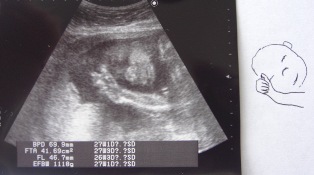

ご心配をおかけしましたが、今日健診を受け、自宅軟禁から解放されました。まだ張り止めの薬は飲み続けるものの、ちょっとずつ社会復帰。突然がんばってはいけません、とは言われたものの、本格的リハビリの再開です。現在26週目(7か月目)ベビの様子。推定体重、1000gぐらいか。今日は顔と手が見えました。だんだん愛情が湧いてきたなぁ。ちなみにわたくしの主治医は、若い女性のドクター。間違いなく年下のはず。たぶん、前回ノスケの帝王切開手術の時に、私の主治医だったドクターとともに、手術室にいたドクター。まだそのころはホントに新米だったと思われる。執刀医はその女医さんに説明をしながら手術を進め、部分麻酔で意識もはっきりしている私はその説明の詳細を聞き、か~な~り、びびった覚えがあります。このドクター、女性だからなのか、エコーに写るベビに対して愛情を持ってくださっており、やっぱり話しやすい。質問にもハキハキ面倒くさがらず答えてくださり、ドクター歴はともかく、私は気が楽です。来週、念のためまた健診。しっかし、いくら無料検診券がたくさんもらえるようになったとはいえ、こういうイレギュラーな診察にはお金がかかります。(\\\\涙)少子化の危機、妊娠出産にかかわることはタダにしてほしいなぁ。。。

年末年始の旅行から帰ってきてすぐに妊娠が発覚し、5ヶ月目に入りました。つわりはだいぶおさまったけど1月半ばからつい最近まで、つわりがきつかった~ケロケロケロリンでした(涙)カナダ生活が残り少なくなるなか、何にもできずダラダラと過ごす時間がもったいなく、ノスケと遊んでやれないこともふがいなく、家のことが満足にできないことも情けなく、なんともフラストレーションのたまった2ヶ月間でした。そして、そんな私を哀れに思っておかずをおすそ分けしてくれたり、ノスケを預かってくれたりした周りの友達には感謝の念でいっぱいです。あと1ヶ月足らずで一時帰国して、私とノスケはそのまま年内、日本に居座り出産予定。ドラさんは一人で5月にオハイオ赴任、およそ8ヶ月間の単身赴任をすることになります。色々迷ったけど、突然行ってドクターが見つかるか、とか、身重で何度も長時間フライトするのはどうか、とか、退院直後に果たしてノスケとベビちゃんの世話を私が一人でみられるか、など、総合的に考えたら(甘えてるかもしれないけれど)やっぱり日本が一番。こうやって家族で暮らせるのもあと1ヶ月ちょっとか。ドラさんが一番寂しいだろうな。私はまだ目先の一時帰国が楽しみすぎてその後のことがなかなか考えられないけど。今日は発覚後2度目の超音波。日本とは違い健診のたびに超音波をしてもらえるわけではないのでとても貴重。日本では言われたことないけど、水を1リットル飲んで膀胱を満タンにしてこいといわれるのはタンクの小さい私には至難の業。でも1リットルも飲まなくても満タンにできるのも私の特技。スクリーンに映るベビちゃんはせわしく手足を動かしていました。気のせいか時々、胎動を感じる気もする。(早すぎるか?)とにかく健康で、悪いところは全部消して生まれてきてね、と願うばかり。